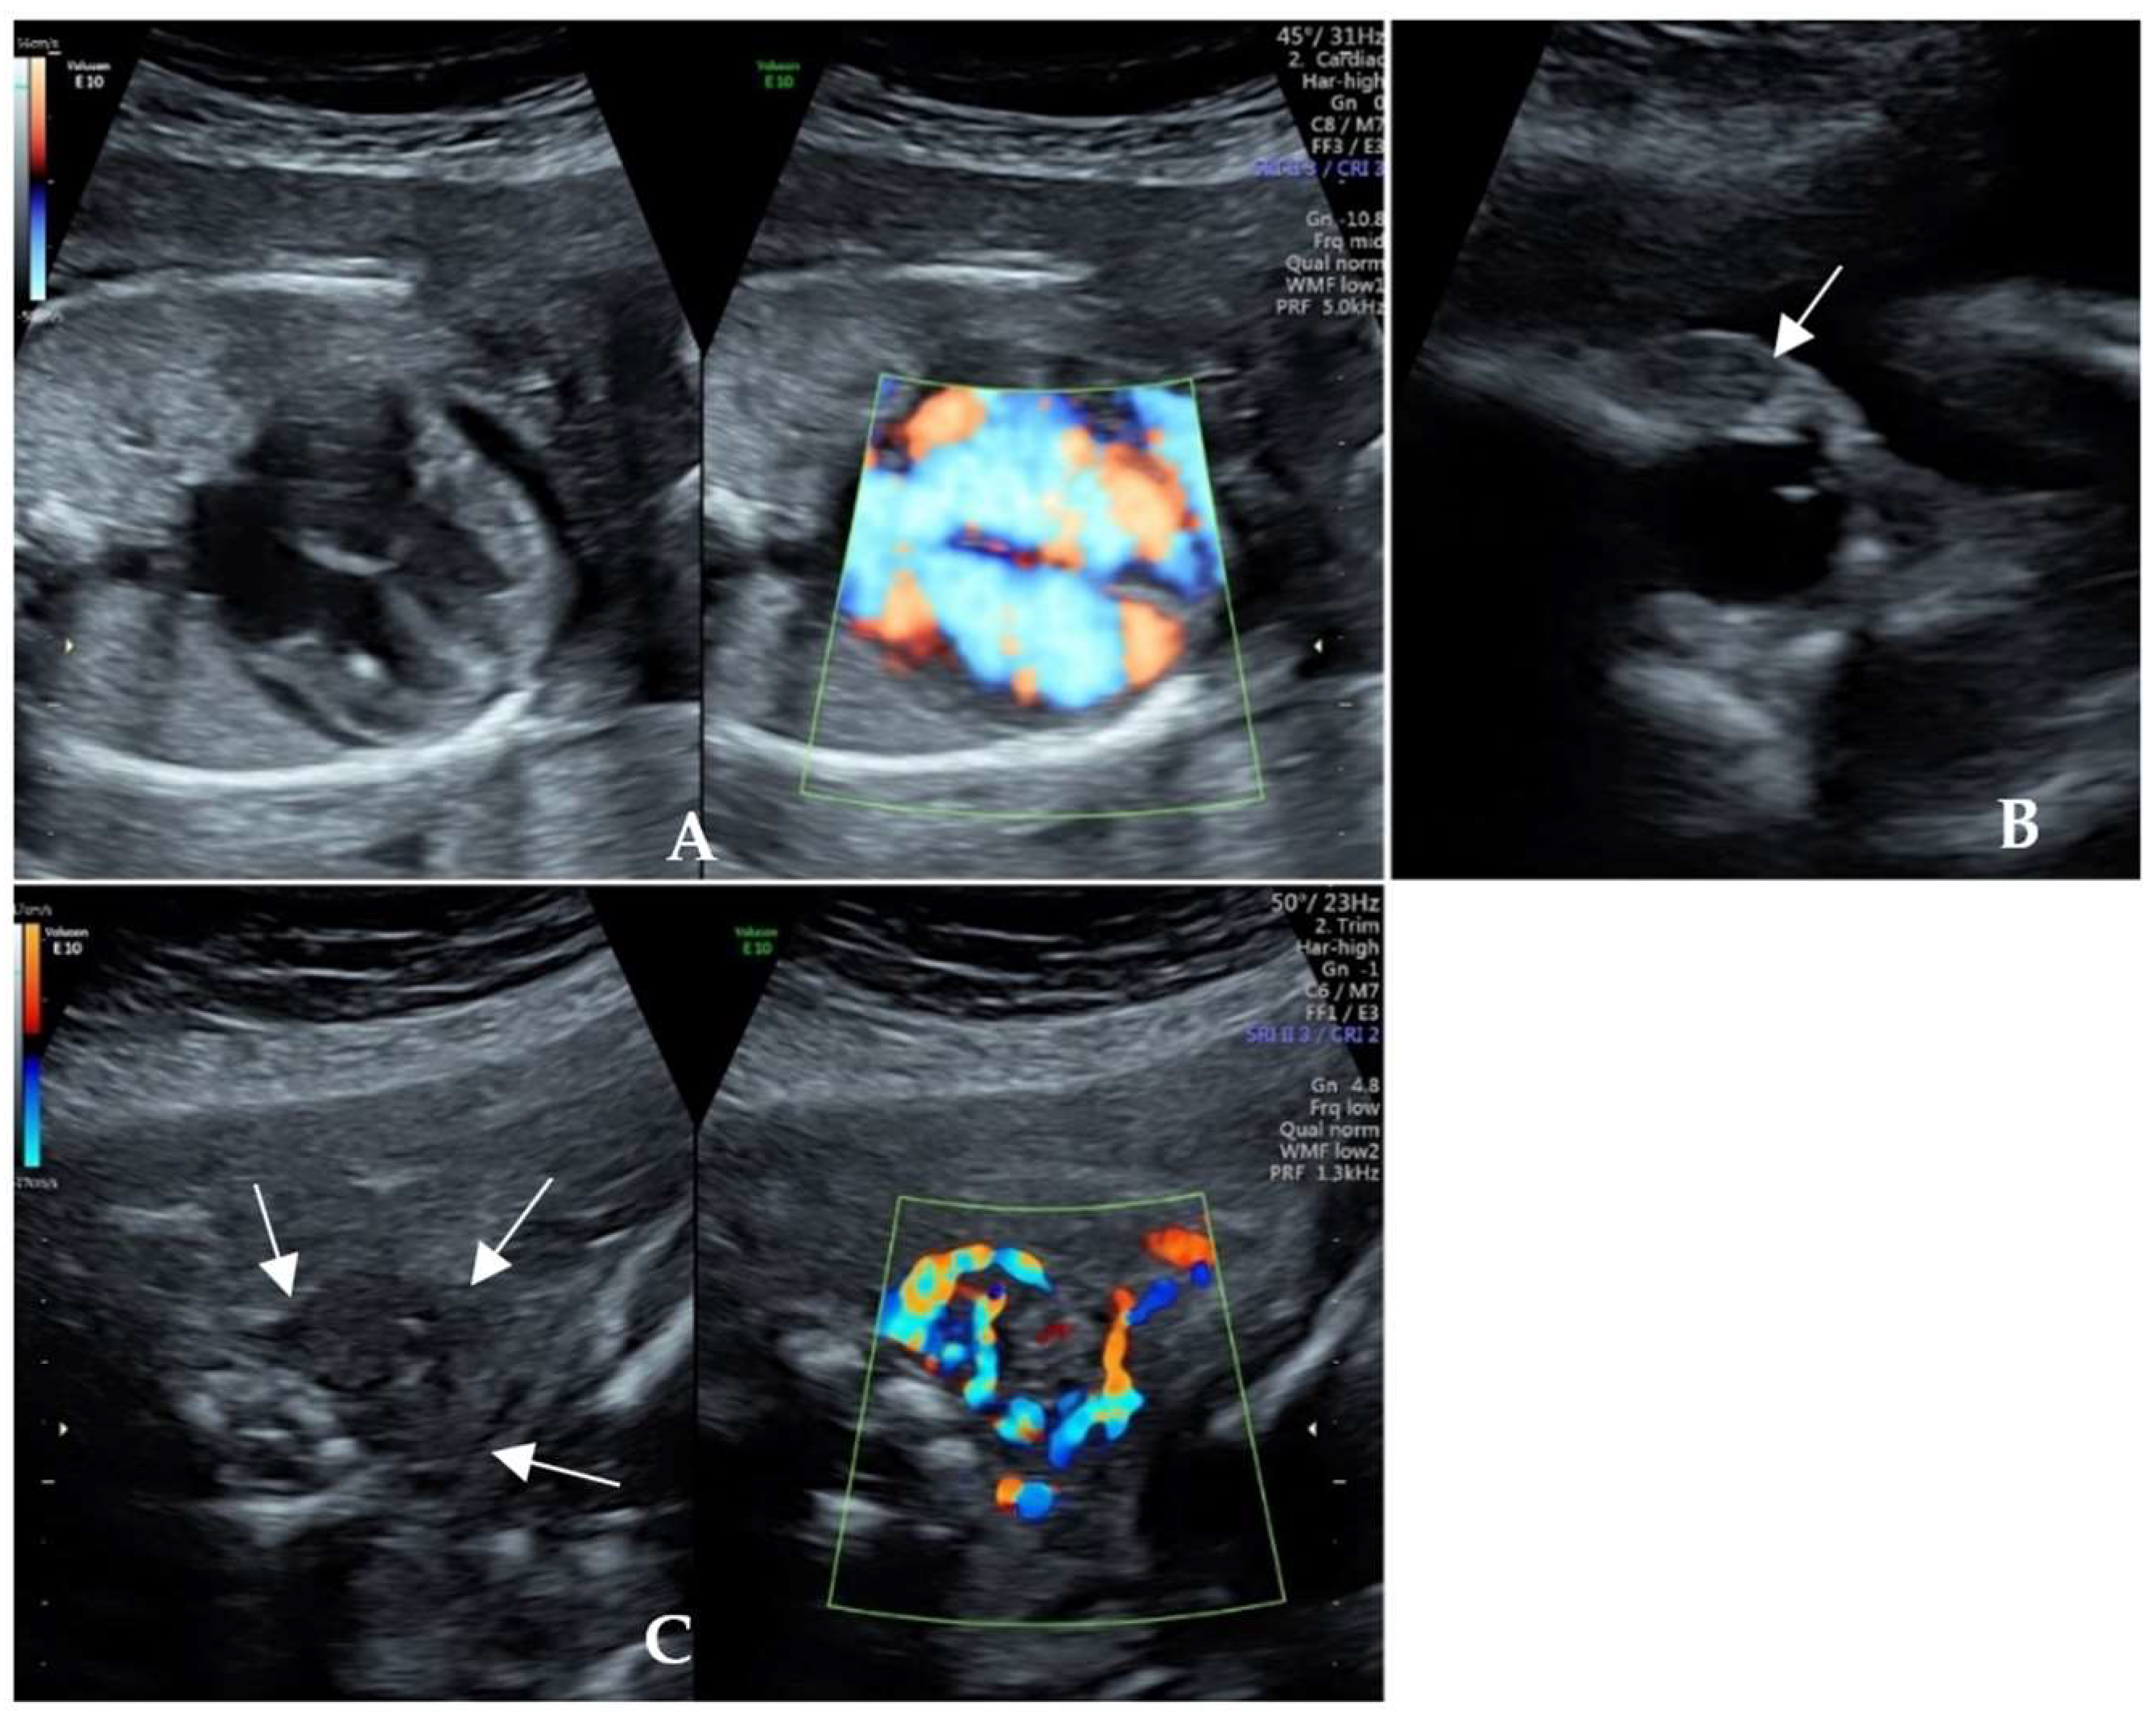

| Fetal manifestations | Fetal cardiac enlargement, pericardial effusion and cardiac hypertrophy, FGR, tachycardia, proptosis, and ventriculomegaly | Fetal tachycardia, enlarged heart and pericardial effusion, tricuspid regurgitation, oligohydramnios, and minor renal dysplasia |

| Fetal thyroid status | Thyroid diffusely enlarged with abundant blood flow, hyperthyroidism (TSH 0.018 μIU/mL and TRAb 32.74 IU/L) | Fetal thyroid gland congested, hyperthyroidism (TSH 0.09 μIU/mL and TRAb 31.9 IU/L) |

| Significant signs of response | The fetal heart rate returned to the normal range 10 days later. The pericardial effusion and cardiothoracic ratio were relieved. | The fetal heart rate returned to normal at the 26th gestational week. Oligohydramnios, cardiac enlargement, pericardial effusion, and thyroid hyperemia were resolved. |